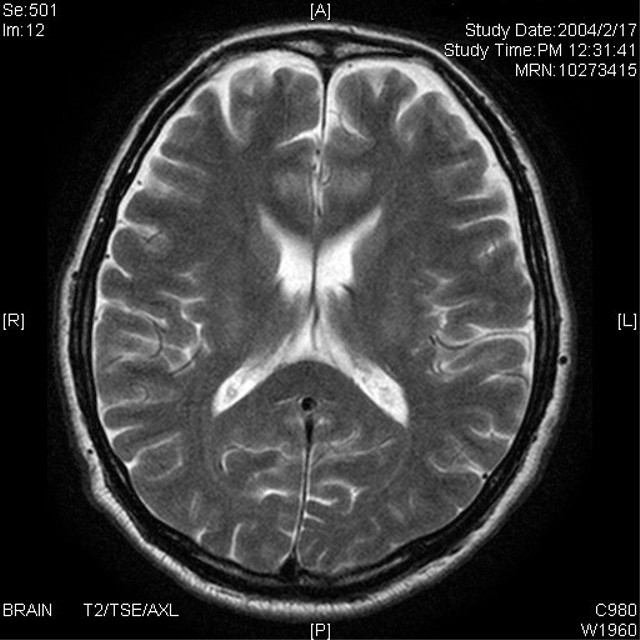

微小出血とは何か:MRIでしか見えない「小さな血の跡」

「脳内の出血」と聞くと、多くの方は脳出血やくも膜下出血のような大出血を想像するかもしれません。しかし、微小出血(cerebral microbleeds)はそれとはまったく異なります。

微小出血とは、脳の毛細血管や細い動脈がもろくなり、ごくわずかな血液が脳組織内に漏れ出た跡のことです。サイズは数ミリ程度で、症状を出さないことが多く、MRIの特殊な撮影法でようやく見つかるレベルです。

肉眼的には出血ではなく「鉄の沈着(ヘモジデリン)」として検出され、黒い点のように写ります。この黒い点が多いほど、脳の血管が傷んでいると考えられます。